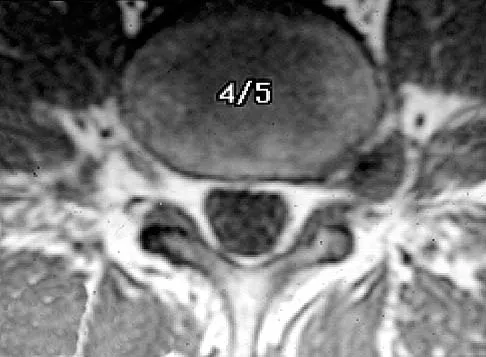

Question 36

The MRI findings shown in Figure 51 would most likely create which of the following signs and symptoms?

Explanation